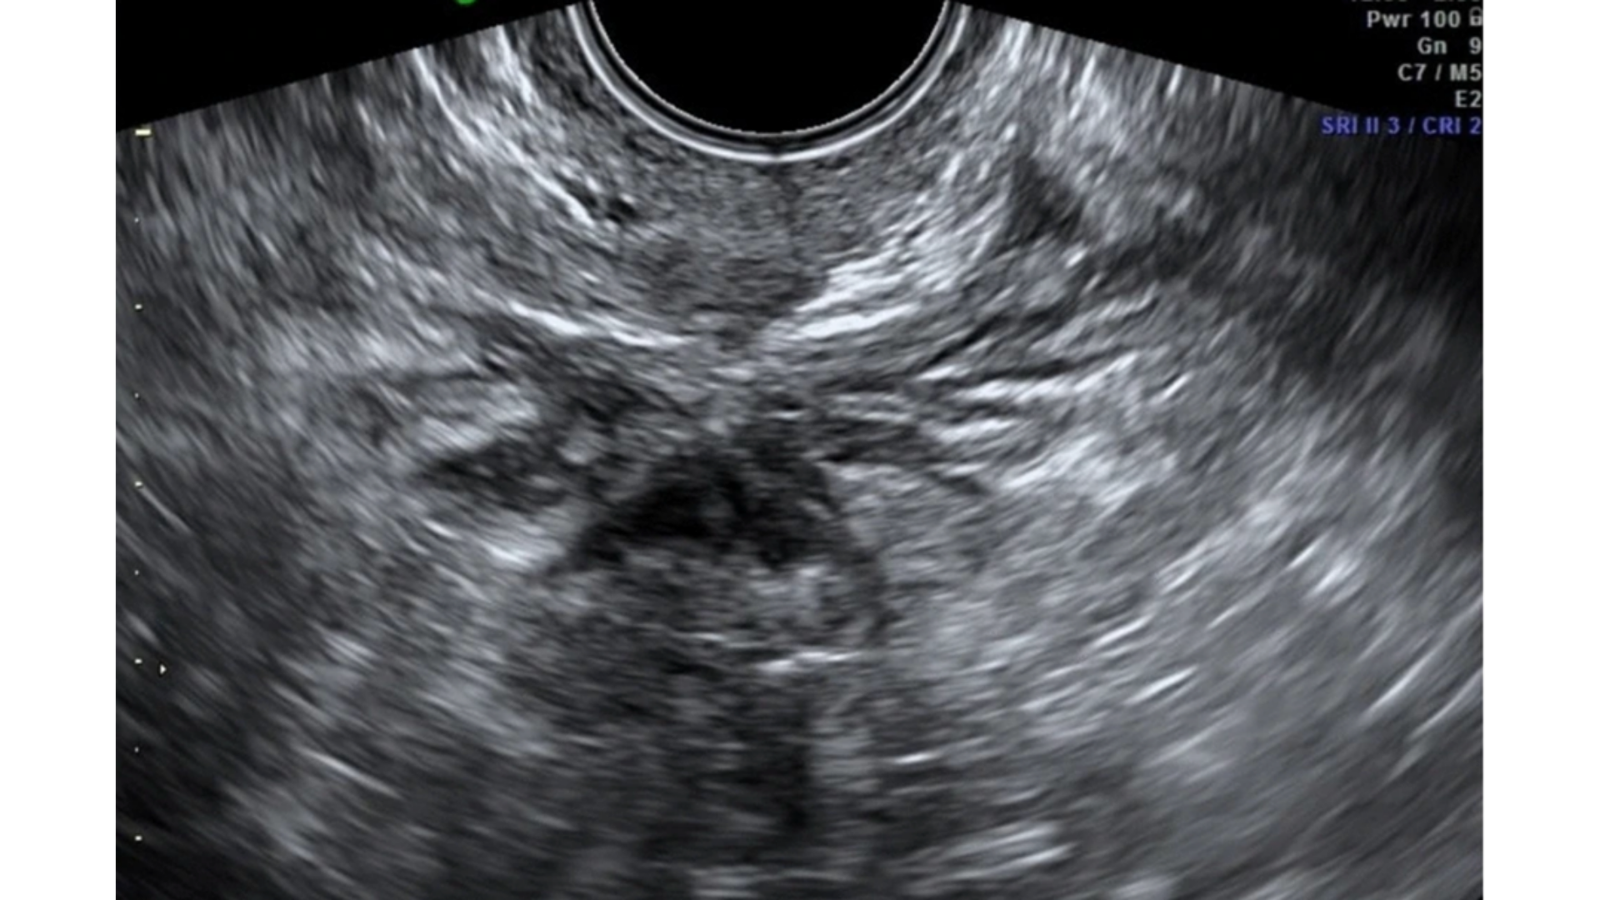

Nódulo hipoecoico de la porción rectosigmoidea que oblitera el Douglas. A este nivel, se puede observar el «signo de deslizamiento», signo del deslizamiento de las estructuras unas sobre otras que no se presenta en el caso de la endometriosis (fig3).

- Signo de deslizamiento (Sliding Sign):Técnica ecográfica dinámica donde se evalúa el movimiento entre el útero y el recto. Si hay deslizamiento, es positivo (no hay adherencias), contrario a lo que se espera en una endometriosis infiltrante de Douglas.